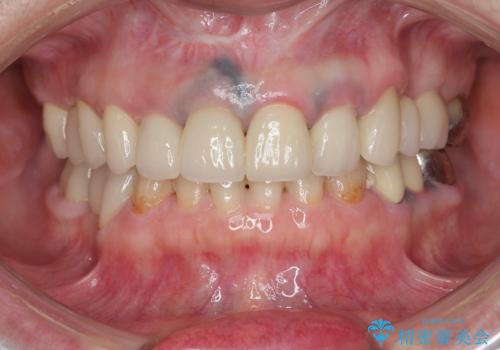

保険適応 硬質レジン前装冠から審美的でオールセラミッククラウンへ

- 変色の進んでしまった前歯を審美的なセラミック治療にしたい、と希望され来院されました。

10数年前に治療を行った保険適応の硬質レジン前装冠は変色劣化が進み、審美的に問題があるだけでなく虫歯のリスクも高くなり好ましくない状況です。

審美的かつ精度の高いセラミック治療を行うことで、汚れがつきにくく虫歯や歯周病の感染リスクを将来にわたって抑える治療が可能になります。

見違えるような審美的な仕上がりに満足いただくことができました。